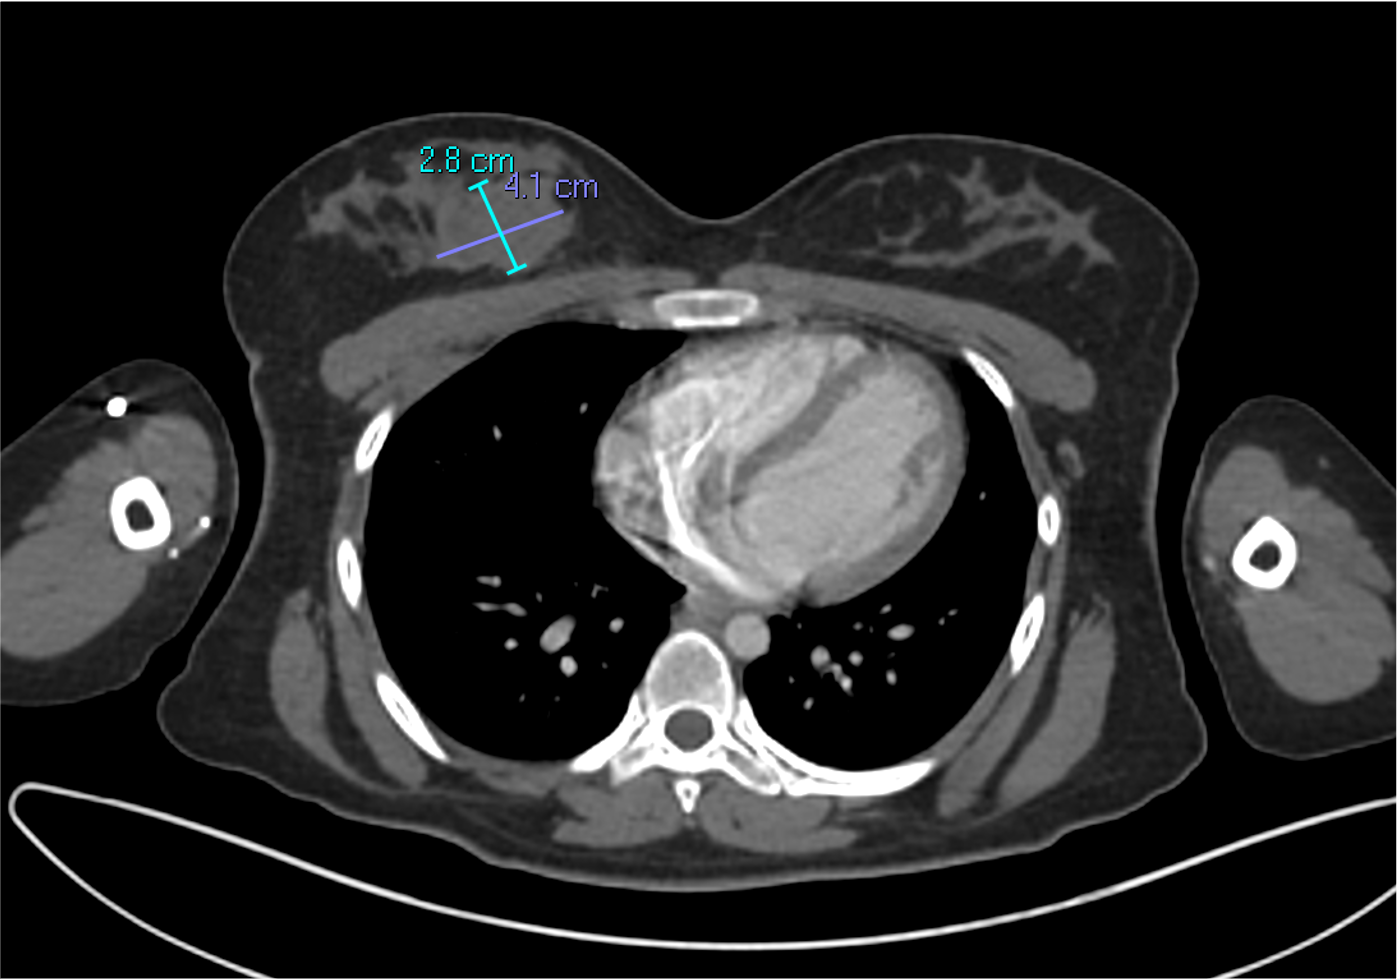

Imágenes de tomografía en adquisición axial en ventana para tejido blando, fase venosa, con su correspondiente correlación con imágenes de PET CT.

F. Mama derecha heterogénea, por la presencia de nódulo de composición sólida, homogénea, con realce periférico tras la administración de medio de contraste, localizado hacia cuadrantes internos y medidas aproximadas de 28×41 mm.

J, K Ganglio subclavio derecho con pérdida de su morfología e hilio graso, con eje corto de hasta 10 mm, con hipermetabolismo